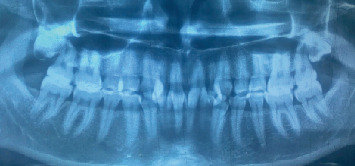

牙齿变色,特别是由于氟中毒,提出了一个显着的审美挑战,许多患者。本文探讨了牙齿漂白和牙釉质微磨损联合使用作为治疗氟中毒引起的变色的有效方法。牙齿漂白是一种广泛应用于减轻外在和内在污渍的方法,在改善变色牙齿的整体外观方面显示出良好的效果。牙釉质微磨蚀,包括机械去除表面牙釉质污渍,可以通过解决更严重或更顽固的变色来提高漂白的有效性。本文综述了这些治疗的机制,它们的临床适应症,以及它们在不同程度的氟牙症患者中的结果。此外,还讨论了潜在的副作用,如牙齿敏感和牙釉质损伤,并强调了减少这些风险的策略。通过结合这些方法,临床医生可以为寻求氟牙美容改善的患者提供更全面,个性化的护理,同时关注美观结果和长期牙齿健康。

Dental discoloration, particularly due to fluorosis, presents a significant aesthetic challenge for many patients. This article explores the combined use of dental bleaching and enamel microabrasion as effective treatments for managing fluorosis-induced discoloration. Dental bleaching, a widely used method for lightening extrinsic and intrinsic stains, has shown promising results in improving the overall appearance of discolored teeth. Enamel microabrasion, which involves the mechanical removal of superficial enamel stains, can enhance the effectiveness of bleaching by addressing more severe or resistant discoloration. The article reviews the mechanisms of these treatments, their clinical indications, and their outcomes in patients with varying degrees of dental fluorosis. Additionally, potential side effects, such as tooth sensitivity and enamel damage, are discussed, emphasizing strategies to minimize these risks. By combining these methods, clinicians can offer more comprehensive, individualized care for patients seeking cosmetic improvements for fluorotic teeth, with attention to both aesthetic outcomes and long-term dental health.